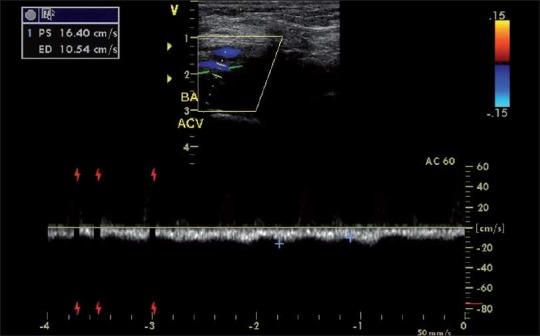

Over the last few years the role of ultrasound has steadily increased and has now an established role in anesthesia and critical care. The various applications of this technology in this field include ultrasound-guided insertion of central lines (internal jugular, subclavian, axillary, femoral) and peripheral venous catheters, arterial line insertion, regional blocks etc. The simple reason of using this technology is "You believe what you see". In this text we will mainly focus on central line, peripheral venous placement and arterial blood flow patterns under ultrasound guidance.In our institution at KFMC, internal jugular vein cannulation is preferred to cannulation of the subclavian vein because of the higher incidence of pneumothorax and subclavian artery puncture associated with the later. The incidence of carotid artery puncture is higher in children younger than five years than in older children during this procedure. The use of ultrasonography has been shown to increase the success rate and decrease the incidence of complications associated with IJV cannulation in adults. We will go through a stepwise approach in identifying and confirming the required blood vessels for ultrasound-guided cannulation using B-mode (2D), color flow doppler and Pulse Wave Doppler.

在过去几年中,超声的作用稳步增强,如今在麻醉和重症监护领域已确立了其地位。该技术在这一领域的各种应用包括超声引导下置入中心静脉导管(颈内静脉、锁骨下静脉、腋静脉、股静脉)和外周静脉导管、动脉置管、区域阻滞等。使用这项技术的简单原因是“眼见为实”。在本文中,我们将主要关注超声引导下的中心静脉置管、外周静脉置管以及动脉血流模式。在我们位于科威特法赫德国王医疗城的机构中,由于锁骨下静脉置管相关的气胸和锁骨下动脉穿刺发生率较高,因此颈内静脉置管比锁骨下静脉置管更受青睐。在此操作过程中,5岁以下儿童的颈动脉穿刺发生率高于大龄儿童。超声检查已被证明可提高成人颈内静脉置管的成功率并降低相关并发症的发生率。我们将采用逐步的方法,使用B超(二维)、彩色多普勒血流显像和脉冲波多普勒来识别和确认超声引导下置管所需的血管。